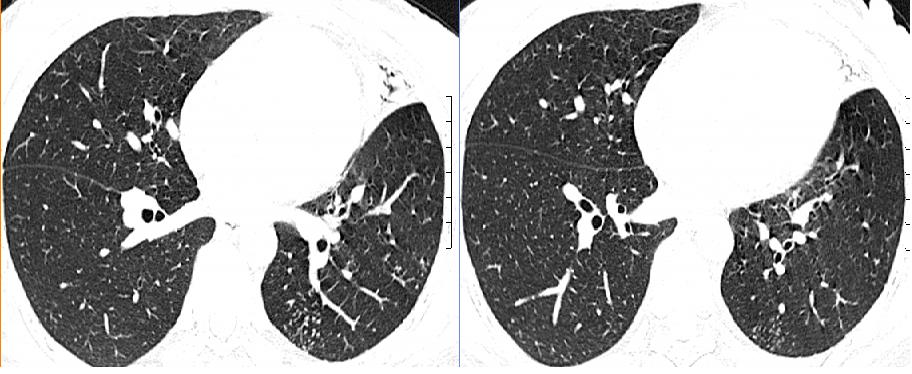

女,33岁,咳嗽5月。

左肺上叶前段致密,内见空气支气管征,相应部位胸膜增厚粘连,双肺上其他肺叶不同程度斑片状播散病灶,结合咳嗽5月的病史,考虑:双肺上叶继发性肺结核。

双上肺、左下肺背段肺结核,左上肺膨胀不全.

左肺上叶前段致密,内见空气支气管征,相应部位胸膜增厚粘连,双肺上其他肺叶不同程度斑片状播散病灶,结合咳嗽5月的病史,考虑:双肺上叶继发性肺结核伴左肺上叶肺含气不良。